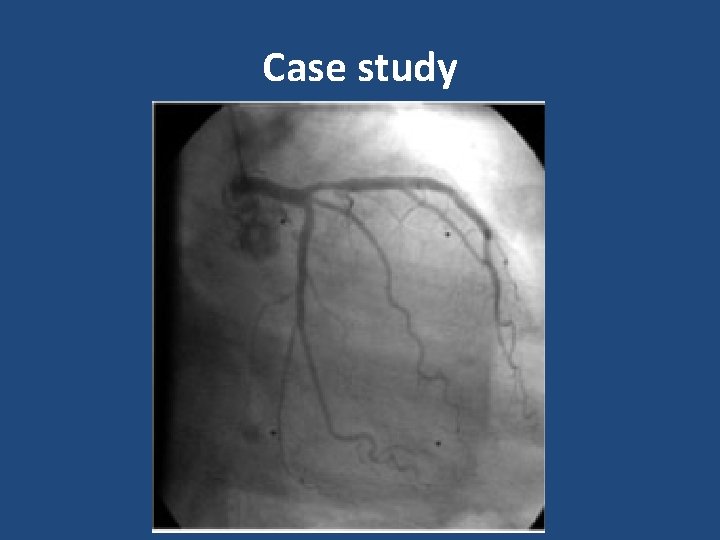

Case study